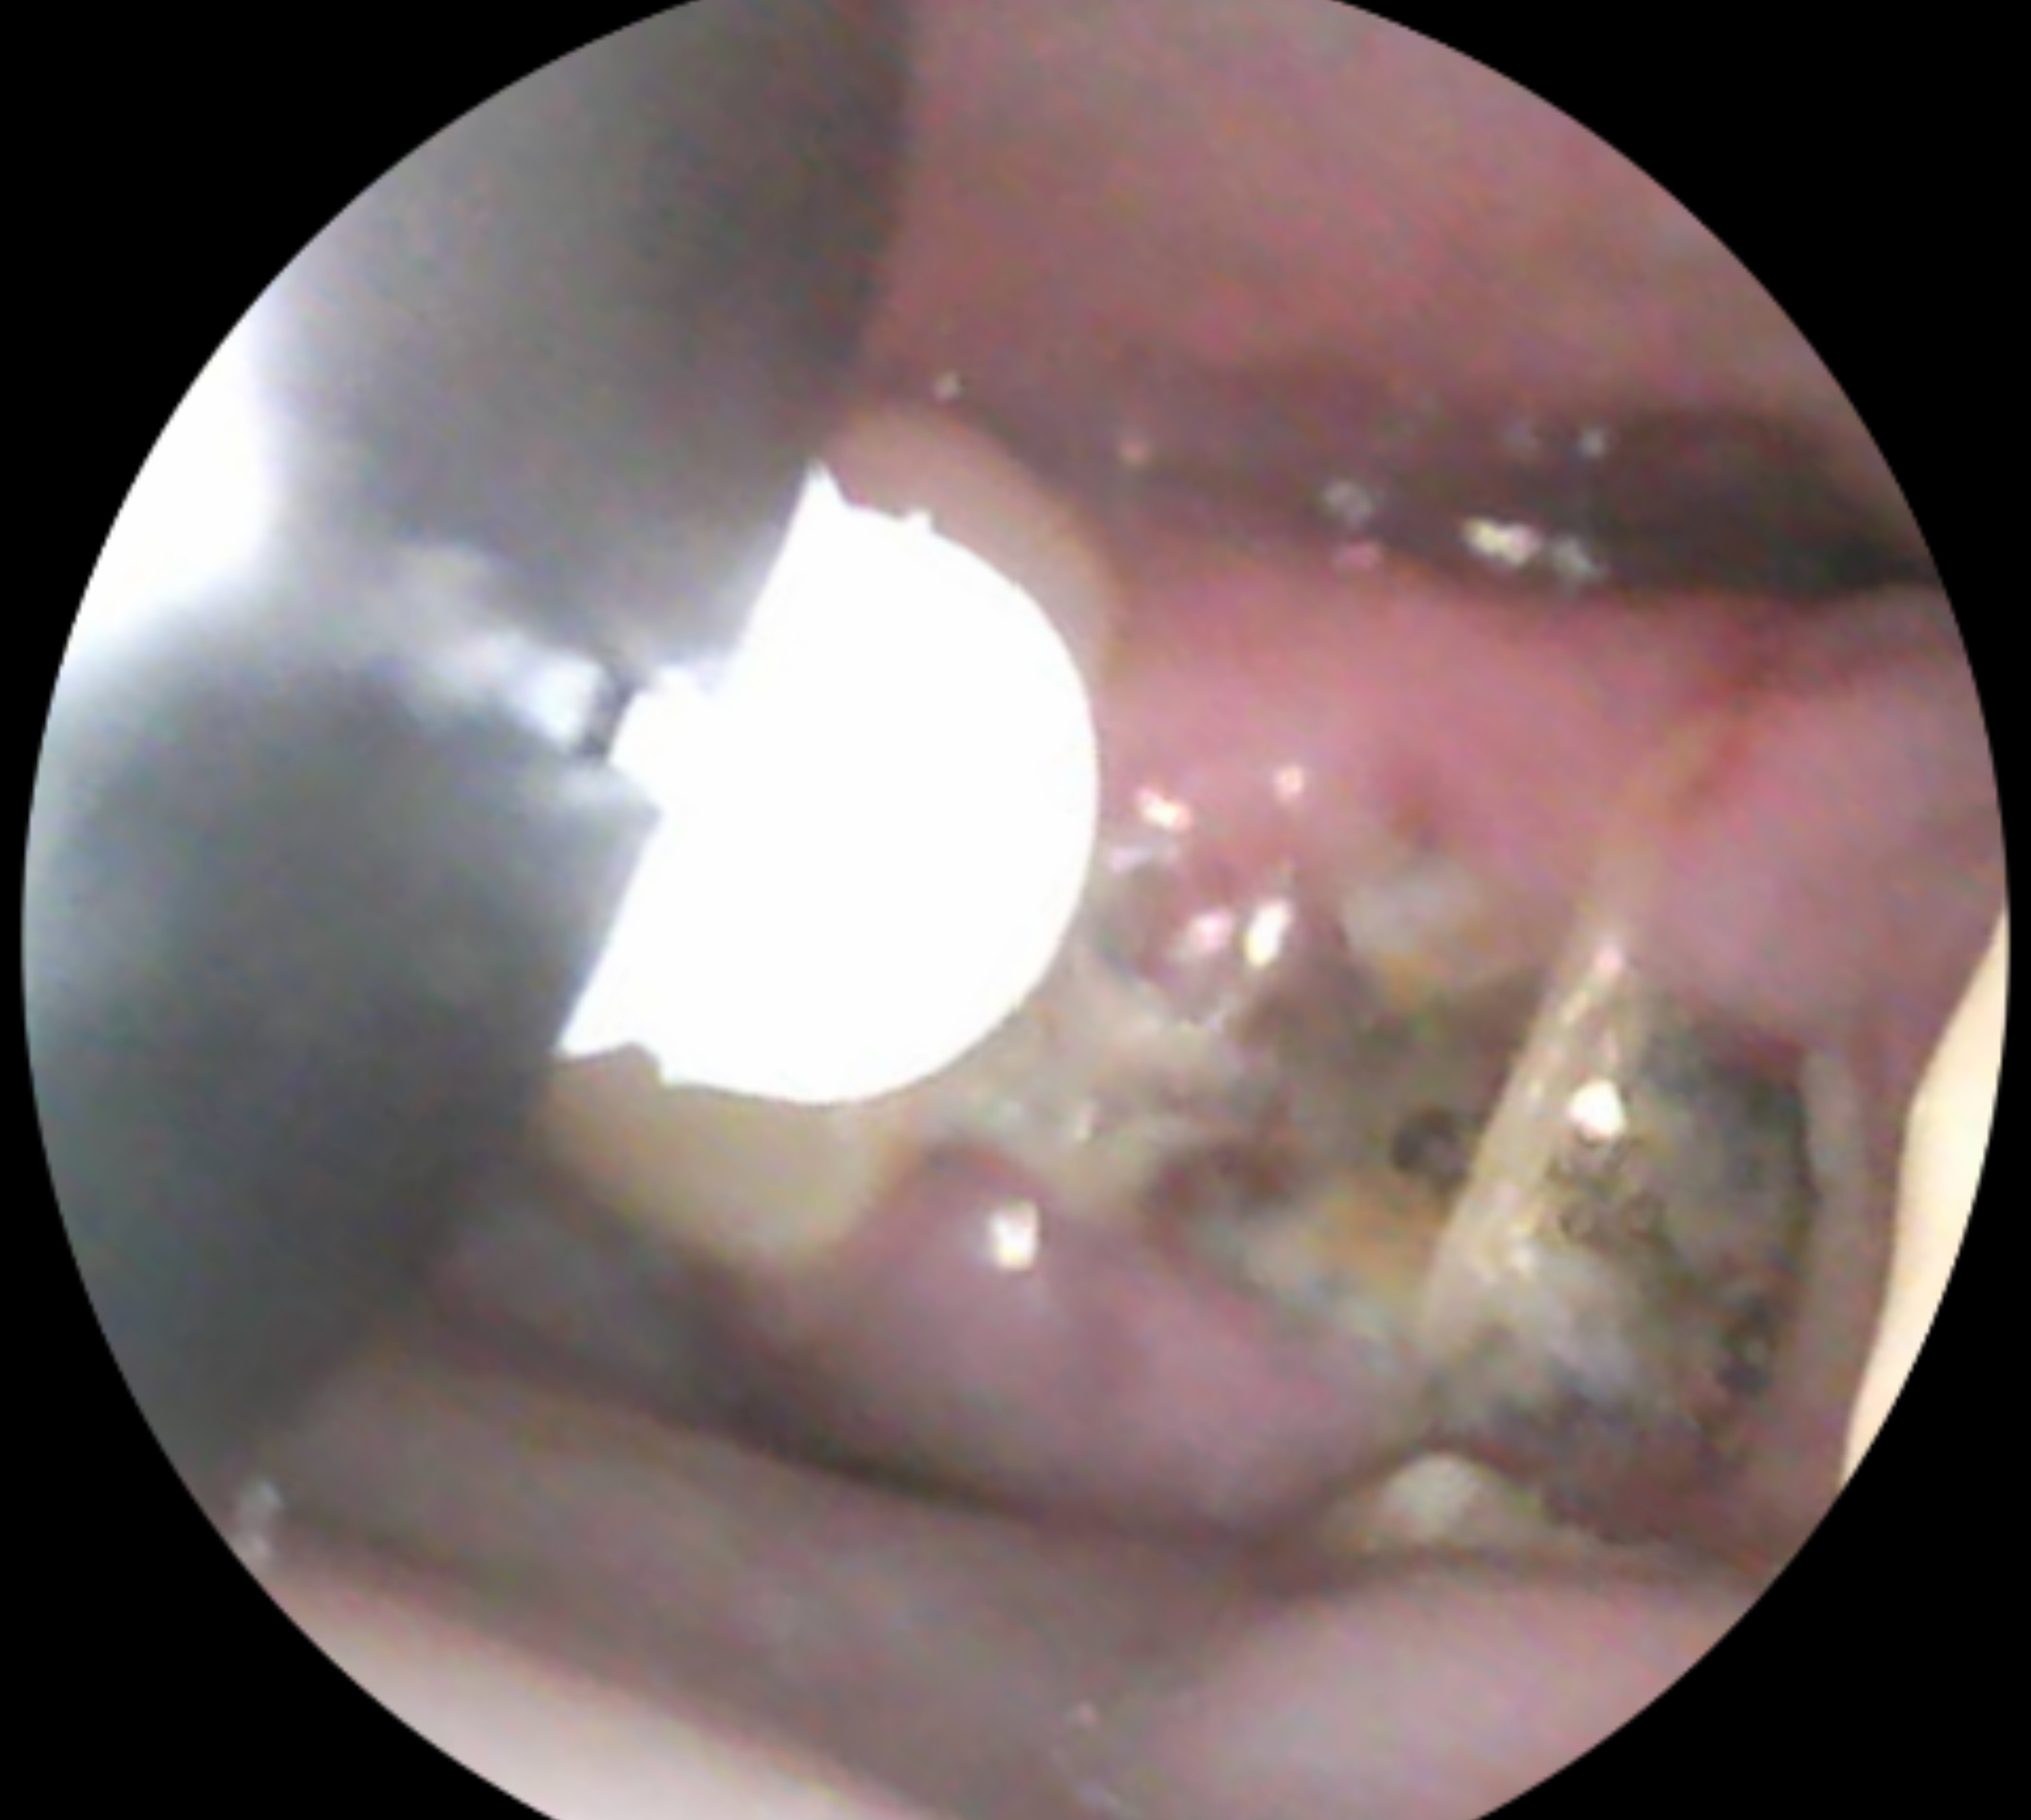

Is this normal healing of extraction sites

I had 2 wisdom and 2 molars removed as of now 5 days ago and these photos were taken on day 3, I was concerned that they may be infected, but there is no pain or outrageous swelling, no bleeding either and I can't really tell if there is a bad smell...